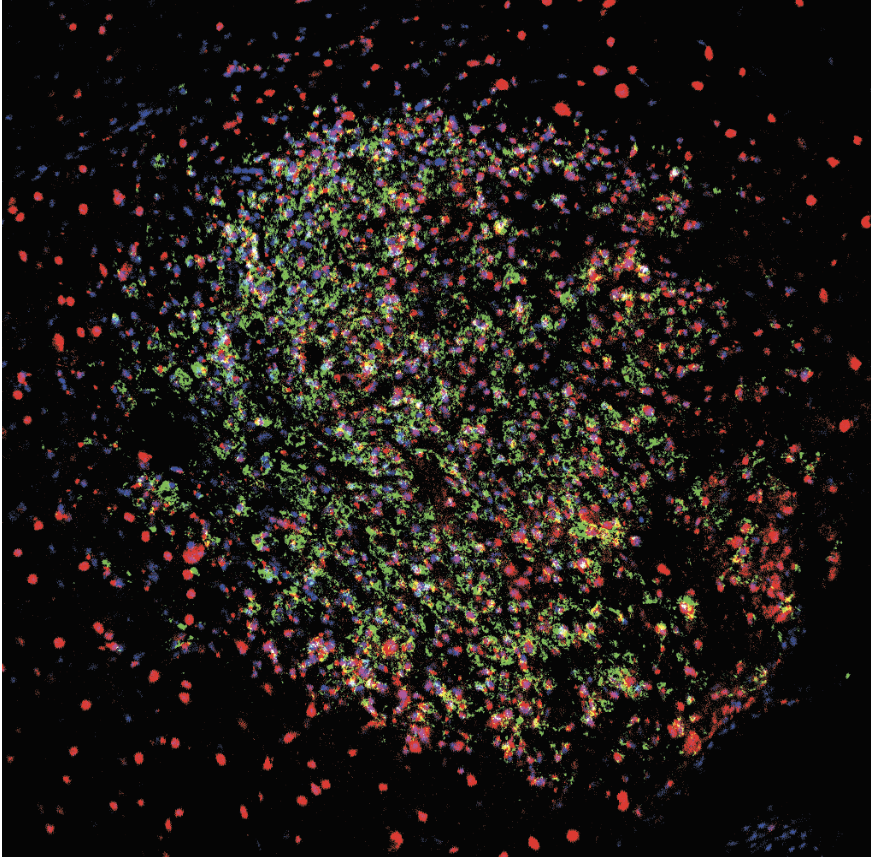

Striking Laboratory Data Images

Laboratory Data Gallery

Universe of the brain